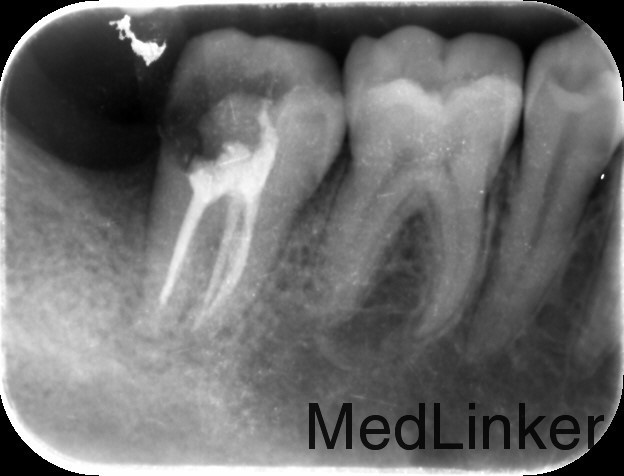

诊断:47牙髓炎 治疗计划:47根管治疗后冠修复。 处置:47碧蓝麻醉下,去腐,降牙合,开髓,揭髓,EDTA伴随下根管预备,冲洗,超声荡洗,干燥,激光消毒,封氢氧化钙。二次复诊:冲洗,试尖,AHplus糊剂和热牙胶充填。

医嘱:勿用患牙咀嚼硬物。 择期冠修复。 讨论:C形根管系统复杂,根管预备时需仔细探查根管,切忌根管遗漏。